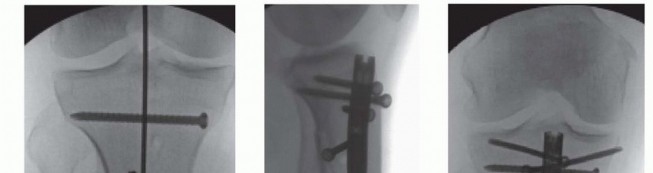

### TECH FIG 10 • A. Maintenance of maximal knee flexion protects the entrance hole from being inadvertently enlarged by the reamer. B. If the guidewire is rotating during reaming, it must be held down as the reamer is pulled back to avoid inadvertent removal of the guidewire. C. A clamp can be used to grasp the guidewire when the reamer head clears the soft tissues. Unreamed Technique Standard preparation technique is used for the starting hole, and the fracture is reduced. Precise evaluation of the lateral isthmic diameter is repeated, and a small-diameter nail is selected, typically in the 7- to 9-mm range. A good guideline is to use a nail 1 to 1.5 mm smaller than the narrowest measure of the isthmus on the lateral radiograph. If lateral plane imaging is suggestive of canal diameter very close to nail size, a single pass with an end-cutting reamer usually is performed to decrease the possibility of nail incarceration. The nail is inserted and impacted in standard fashion. If significant resistance is encountered when the nail reaches the isthmus, the nail is removed to avoid incarceration or iatrogenic fracture propagation. A reamer 0.5 to 1.0 mm larger than the nail is passed down the canal, and nail passage is attempted again. Nail Insertion Once the nail insertion handle is attached, pass a drill through the proximal screw insertion attachment and screw insertion cannulas before inserting the nail to ensure accurate alignment of the attachment jig. Maintain nail rotation during insertion by aligning the center of the insertion handle with the tibial crest. Consider internal rotation of the nail if distal AP interlocking bolts are deemed necessary to minimize damage to distal neurovascular structures. Maintain knee hyperflexion during nail insertion to minimize the risk of posterior cortical abutment and iatrogenic fracture. Impact the nail to the final depth using lateral plane fluoroscopy. Interlocking Bolt Insertion In simple transverse fractures, place distal interlocks first to allow for backslapping for interfragmentary compression and gap minimization. Usually, distal interlock bolts are placed medial to lateral. Position the leg in slight extension and stable neutral rotation. 559 Rotate the C-arm to lateral imaging position and pull the tube back away from the medial side of the leg to allow for drill placement. Rotate the leg and C-arm individually and sequentially to create a perfect circle image; optimize this view before drilling attempts ( TECH FIG 11A). After localizing the interlocking hole using a clamp and fluoroscopy, make an incision large enough to place the locking bolt. Use blunt clamp dissection until the cortex is reached. Use a sharp drill point and place the center of the point in the center of the circle. Hold the drill obliquely to the nail axis to simplify repositioning ( TECH FIG 11B). Once the central location is achieved; align hand and drill with imaging axis. Fluoroscopes with laser alignment guides can be helpful to assist with alignment by centering the laser on the skin incision and then placing the laser in the center of the back of the drill when preparing to drill the hole ( TECH FIG 11C). Drill to the midsagittal point in the tibia. Then, disengage the drill from the drill bit and check the fluoroscopic image. If the drill is accurately positioned in the center of the hole, advance the drill bit with power through the far cortex; avoid broaching the far cortex by impacting with a mallet to avoid iatrogenic fracture. Drill the second interlock hole using the same technique but maintaining a parallel axis with the first successful drill passage. Replace the drill with the appropriate depth gauge and check an AP image before screw length selection. Once interlock lengths and position are verified, “backslapping” can occur to optimize compression. Using the slotted mallet attachment on the insertion handle, superiorly directed mallet blows can be used while pressure is applied to the foot in order to compress the fracture site. Fluoroscopy should be used to monitor the amount of compression and the nail position proximally. If backslapping is planned, the nail should be slightly overinserted to avoid nail prominence after compression is performed.

### TECH FIG 11 • A. A perfectly rotated lateral fluoroscopic image will appear as a perfect circle and should be achieved before drilling is attempted. B. The drill point must be aligned in the center of the perfect circle before drilling. C. The laser alignment guide can be helpful for localizing the skin incision. Place proximal interlocks through drill guides. Because the tibia is a triangle, oblique views may be used to more accurately judge screw length for transverse locking bolt measurement. If oblique locking bolts are chosen proximally, oblique fluoroscopic views should be used prior to insertion handle removal to avoid placing long screws that are particularly symptomatic on the medial side of the knee and to avoid injury to the peroneal nerve posterolaterally. ### Lateral Parapatellar Tendon Approach After completing the lateral parapatellar approach described, the standard patient positioning is used. The lateral parapatellar approach allows the guide pin to be more easily placed just medial to the lateral tibial spine on the AP view and along the lateral cortex to correct the valgus angulation. If a true AP view is not obtained and the leg is externally rotated, the starting point will be more medial than desired. 4 It is important to get enough knee flexion over the radiolucent triangle or bolster to allow for the guide pin to be placed as proximal as possible and parallel along the anterior tibial cortex to help correct the typical flexion deformity. 20 ### Semiextended Technique The benefit of the semiextended technique is that the leg position helps neutralize the associated flexion deformity. 26 The patient is placed in the semiextended position as described earlier. The open medial parapatellar approach can be used (see TECH FIG 2). Using the previously described surgical approach, the patella is subluxated to allow for guide pin placement, reaming, and nail placement, with the knee remaining in the semiextended position. No special instruments are required. Suprapatellar approach 28 Either the superomedial or direct superior approach is used. Special instrumentation is required; which instrumentation is needed depends on the specific system used. 560 The patella is subluxated using an elongated cannula ( TECH FIG 12A). The cannula is advanced to the standard starting point using fluoroscopy. The guide pin is placed in the standard position (TECH FIG 12B). The typical steps—using the opening drill, placing the guidewire, and reaming—are all completed through the elongated cannula. Standard intramedullary reamers can be used but reamer extensions are helpful, especially in taller patients. Fracture reduction and passing of the guidewire are performed before reaming. A special elongated nail insertion handle is required for nail insertion ( TECH FIG 12C). Proximal locking bolt insertion is done using the aiming arm. Distal locking bolts are placed using the standard freehand technique, as previously described. ### Adjunct Reduction and Fixation Techniques Blocking/Pöller Screws Screws can be placed across the intramedullary canal to create a “false” cortex outside of the isthmus that narrows the potential space for the nail. This aids in both fracture reduction as the nail is being placed and maintenance of the reduction once the nail is seated. 13, 24

- C. A specialized, long insertion handle is required for suprapatellar techniques to reach the tibial start site. Locking bolts found in the nailing set or screws made from the same metal as the nail should be used. Blocking screws can either be placed prior to initial nail insertion or, if the nail is inserted and residual deformity exists, the nail can be removed and blocking screws can be inserted. Coronal and sagittal plane correction can be performed by placing a screw at the concavity of the deformity. To correct valgus, the screw is placed laterally ( TECH FIG 13A). To correct lateral plane extension, the screw is placed posteriorly (TECH FIG 13B). The appropriately sized drill bit is placed with fluoroscopic assistance. The appropriately sized screw replaces the drill bit. The guidewire is then inserted and seated distally. Intramedullary reaming is necessary to ensure the nail follows the newly created path. When a screw that blocks the way is encountered, simply push the reamer head past the screw without reaming. This avoids dulling the reamer head and potentially displacing the blocking screw. Once passed the screw, resume reaming. After reaming is complete, insert the intramedullary nail. If the displacement has not been corrected, it will be necessary to remove the nail, and additional screws may be added. Reaming and reinsertion of the guidewire are required before reinserting the nail. Interlocking bolts through the nail are placed in the standard fashion ( TECH FIG 13B,C). 561 ### TECH FIG 13 • A. A blocking screw positioned just lateral to the ideal nail path to prevent valgus deformation.

| ### B. A posterior blocking screw limits proximal fragment extension by limiting the effective anterior to posterior canal diameter. B,C. Lateral and AP fluoroscopic imaging showing oblique and medial to lateral interlocking bolts placed through the nail.